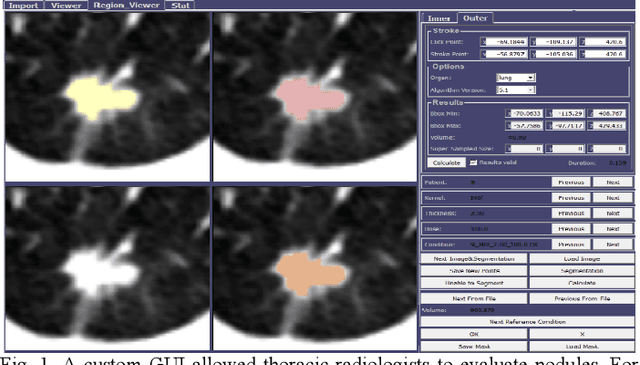

Abstract:Consistency and duplicability in Computed Tomography (CT) output is essential to quantitative imaging for lung cancer detection and monitoring. This study of CT-detected lung nodules investigated the reproducibility of volume-, density-, and texture-based features (outcome variables) over routine ranges of radiation-dose, reconstruction kernel, and slice thickness. CT raw data of 23 nodules were reconstructed using 320 acquisition/reconstruction conditions (combinations of 4 doses, 10 kernels, and 8 thicknesses). Scans at 12.5%, 25%, and 50% of protocol dose were simulated; reduced-dose and full-dose data were reconstructed using conventional filtered back-projection and iterative-reconstruction kernels at a range of thicknesses (0.6-5.0 mm). Full-dose/B50f kernel reconstructions underwent expert segmentation for reference Region-Of-Interest (ROI) and nodule volume per thickness; each ROI was applied to 40 corresponding images (combinations of 4 doses and 10 kernels). Typical texture analysis metrics (including 5 histogram features, 13 Gray Level Co-occurrence Matrix, 5 Run Length Matrix, 2 Neighboring Gray-Level Dependence Matrix, and 2 Neighborhood Gray-Tone Difference Matrix) were computed per ROI. Reconstruction conditions resulting in no significant change in volume, density, or texture metrics were identified as "compatible pairs" for a given outcome variable. Our results indicate that as thickness increases, volumetric reproducibility decreases, while reproducibility of histogram- and texture-based features across different acquisition and reconstruction parameters improves. In order to achieve concomitant reproducibility of volumetric and radiomic results across studies, balanced standardization of the imaging acquisition parameters is required.